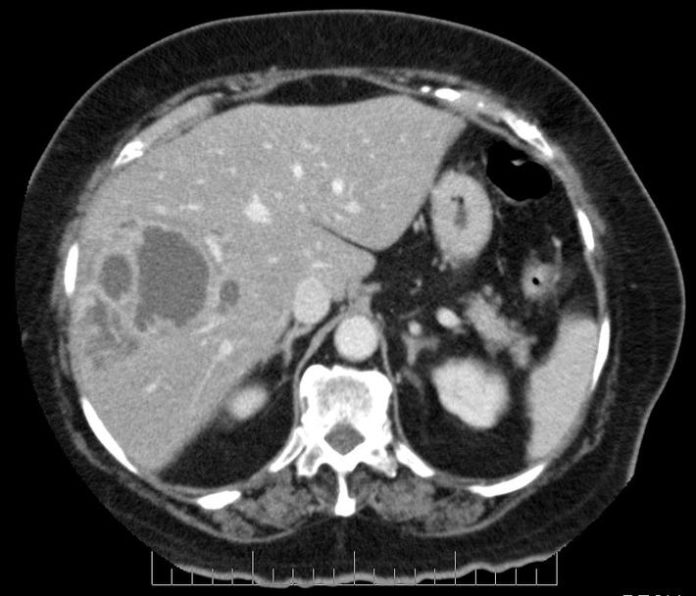

Liver Abscess CT Scan Abscess On Liver Learn about the causes, symptoms and treatment of liver abscesses, which are collections of pus in the liver. Common causes include infective colitis, cholecystitis, cholangitis, diverticulitis, or appendicitis. Liver abscess is a localized infection in the liver parenchyma that may be bacterial, fungal, or parasitic in origin. Learn about the causes, symptoms, and treatments of liver abscess, a severe infection. Abscess On Liver.

Liver abscess, CT scan Stock Image C026/7956 Science Photo Library Abscess On Liver Learn about the causes, symptoms, and treatments of liver abscess, a severe infection that forms in the liver. Liver abscess is a localized infection in the liver parenchyma that may be bacterial, fungal, or parasitic in origin. A liver abscess typically results from a bacterial infection spreading from the biliary or gastrointestinal tract, either via contiguous spread or seeding from. Abscess On Liver.

Liver abscess, CT scan Stock Image C026/7955 Science Photo Library Abscess On Liver Learn about the causes, symptoms and treatment of liver abscesses, which are collections of pus in the liver. Liver abscess is a localized infection in the liver parenchyma that may be bacterial, fungal, or parasitic in origin. For pyogenic liver abscess(es), positive blood cultures are seen in up to 50%. A liver abscess typically results from a bacterial infection spreading. Abscess On Liver.